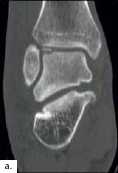

Die Diagnose einer OSG-Distorsion, die später als Grundlage einer adäquaten Therapie dient, ergibt sich aus der Kombination von Befunden verschiedener diagnostischer Ebenen (Anamnese, klinische Untersuchung, bildgebende Diagnostik). Die Erstdiagnostik nach dem Unfall beinhaltet Röntgenaufnahmen des OSG in zwei Ebenen. Im Verlauf und bei persistierenden Beschwerden können MRT- (Abb. 2) oder CT-Aufnahmen angefertigt werden, um Begleitverletzungen wie osteochondrale Frakturen (Abb. 3a), Syndesmosenverletzung oder Peronealsehnenaffektion (Abb. 3b) nachzuweisen.